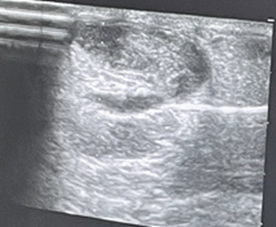

En corte longitudinal, se observa el tendón de Aquiles engrosado, hipoecogénico, con pérdida de la arquitectura fibrilar compatible con tendinosis, además de irregularidad focal compatible con secuela de rotura parcial. En corte transversal destaca calcificación intrasustancia y cambios degenerativos. Paratendón inferior y superior engrosados. Grasa de Hoffa con aumento de ecogenicidad sugerente de inflamación.